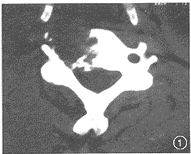

入院查体:神清,一般状况良好,血压105/68mmHg,头面部明显向左侧偏斜,右颈部沿胸锁乳突肌方向有约4cm×3cm×7cm肿块,质硬,无压痛,边界不清,活动差,挤压肿块未见血压变化,其上有2.5cm术后瘢痕,肿块处未闻及血管杂音。生化检查均正常。颈部CT(图1)及立体成像示:C5椎体右侧及横突骨质破坏。MRI示:C5椎体病灶及颈部右侧两个团块状肿块。术前诊断:颈部恶性肿瘤。

图1颈椎CT示C5椎体破坏